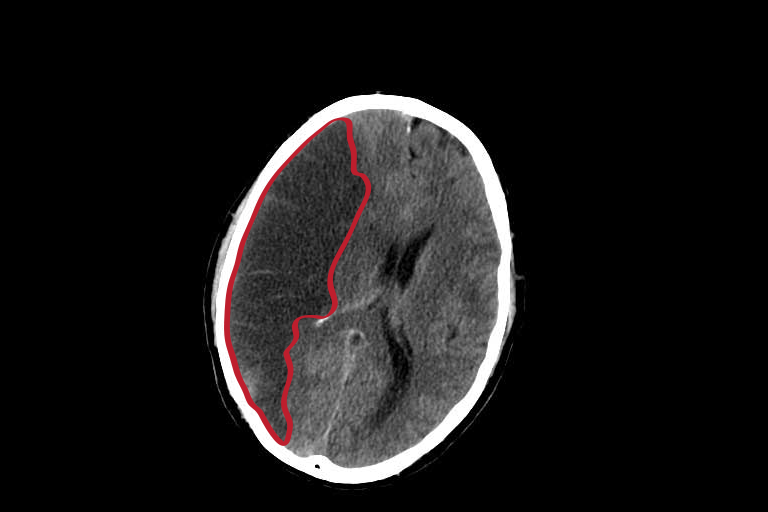

Un ictus, también llamado accidente cerebrovascular (ACV), infarto cerebral, trombosis o embolia, es una enfermedad cerebrovascular que produce un déficit del flujo sanguíneo en el cerebro.